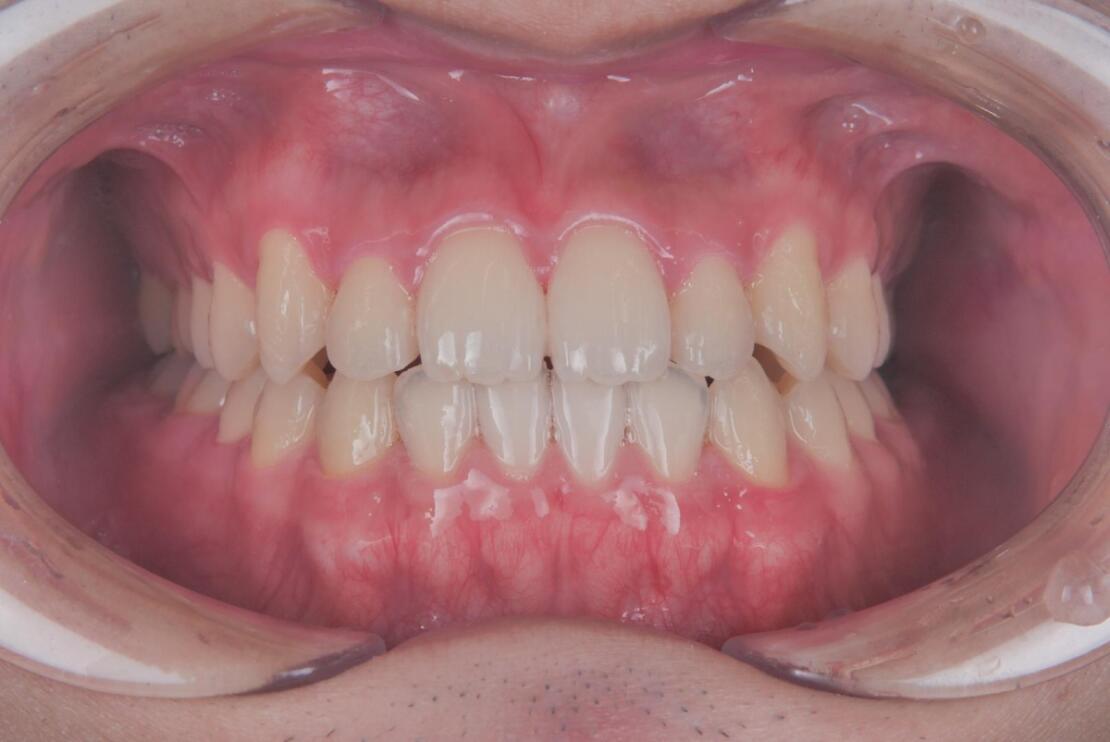

After 1

After 2